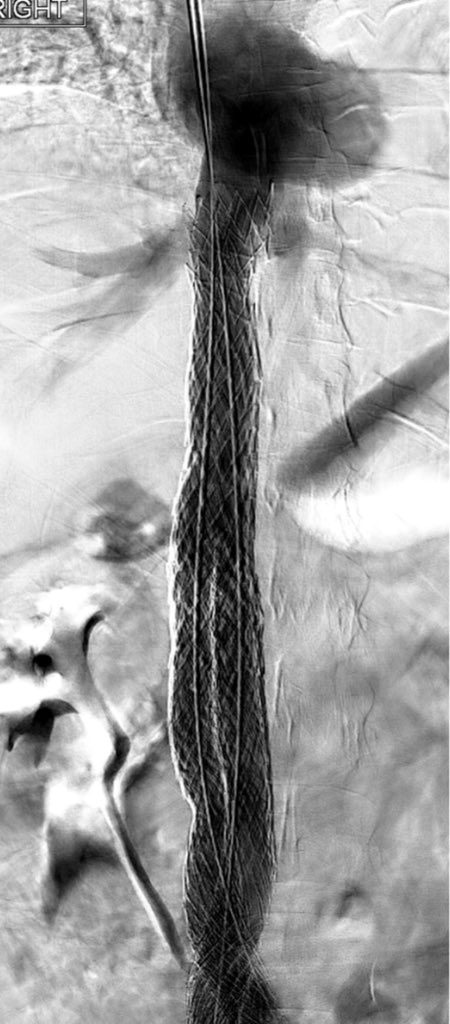

@ChengaziMD @t_intheleadcoat @SDhandMD @drochohan @kmadass @JayMathewsMD @CHICKVIR @Dr_Sudi @DrJayMohan @hkdamonster @SyedYNaqvi1 Nice save with minimal XR, a little IVUS as well? Lucky to have your expertise. I’ve also been preferring IJ when possible